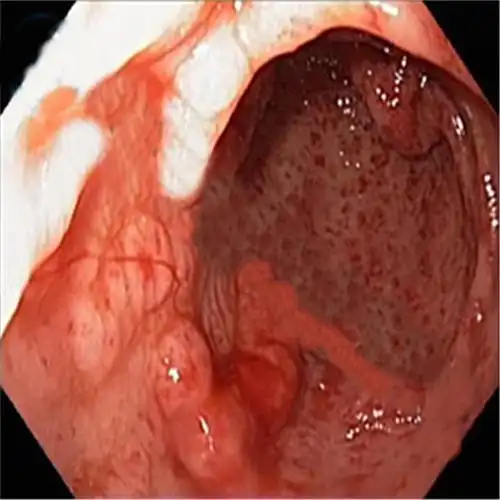

胃镜检查慢性浅表性胃炎 可图片怎么看起来表面突肿

胃不舒服,持续天天打嗝一年,胃镜诊断为慢性浅表性胃炎(隆起糜烂型)